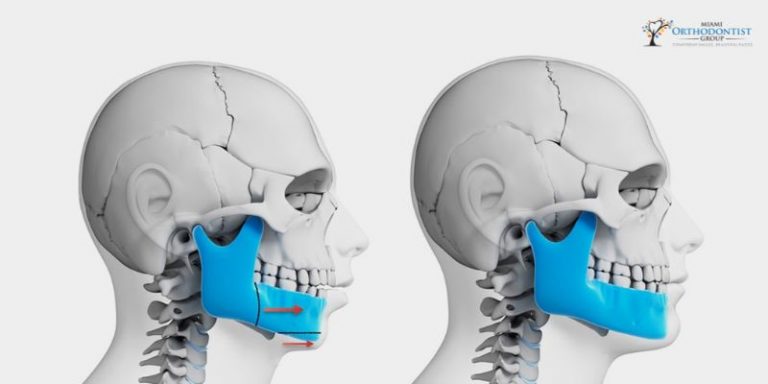

How Can Orthognathic Surgery Treat Sleep Apnea?

www.miamiorthodontistgroup.comOrthognathe Chirurgie | MKG-Lösungen | Materialise

www.miamiorthodontistgroup.comOrthognathe Chirurgie | MKG-Lösungen | Materialise